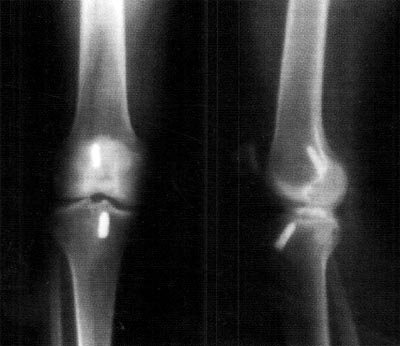

En el examen físico se constató limitación de 5° en la extensión de la rodilla acompañada con dolor sin referir un traumatismo evidente. Las radiografías no mostraron alteración osea y ubicación correcta de los tornillos interferenciales (Fig.1). La RM evidenció la presencia de un nódulo de 1,3 cm de espesor de baja señal compatible con tejido fibroso nivel del túnel intercondíleo inmediatamente anterior al injerto (Fig.2). Ante los hallazgos del examen físico y los estudios complementarios, se le realizó una artroscopia en diciembre del 2002.

10_02_08_fig1

Figura. 1: Imagen radiográfica de rodilla frente y perfil que evidencia buena localización de los túneles óseos con los tornillos de interferencia.